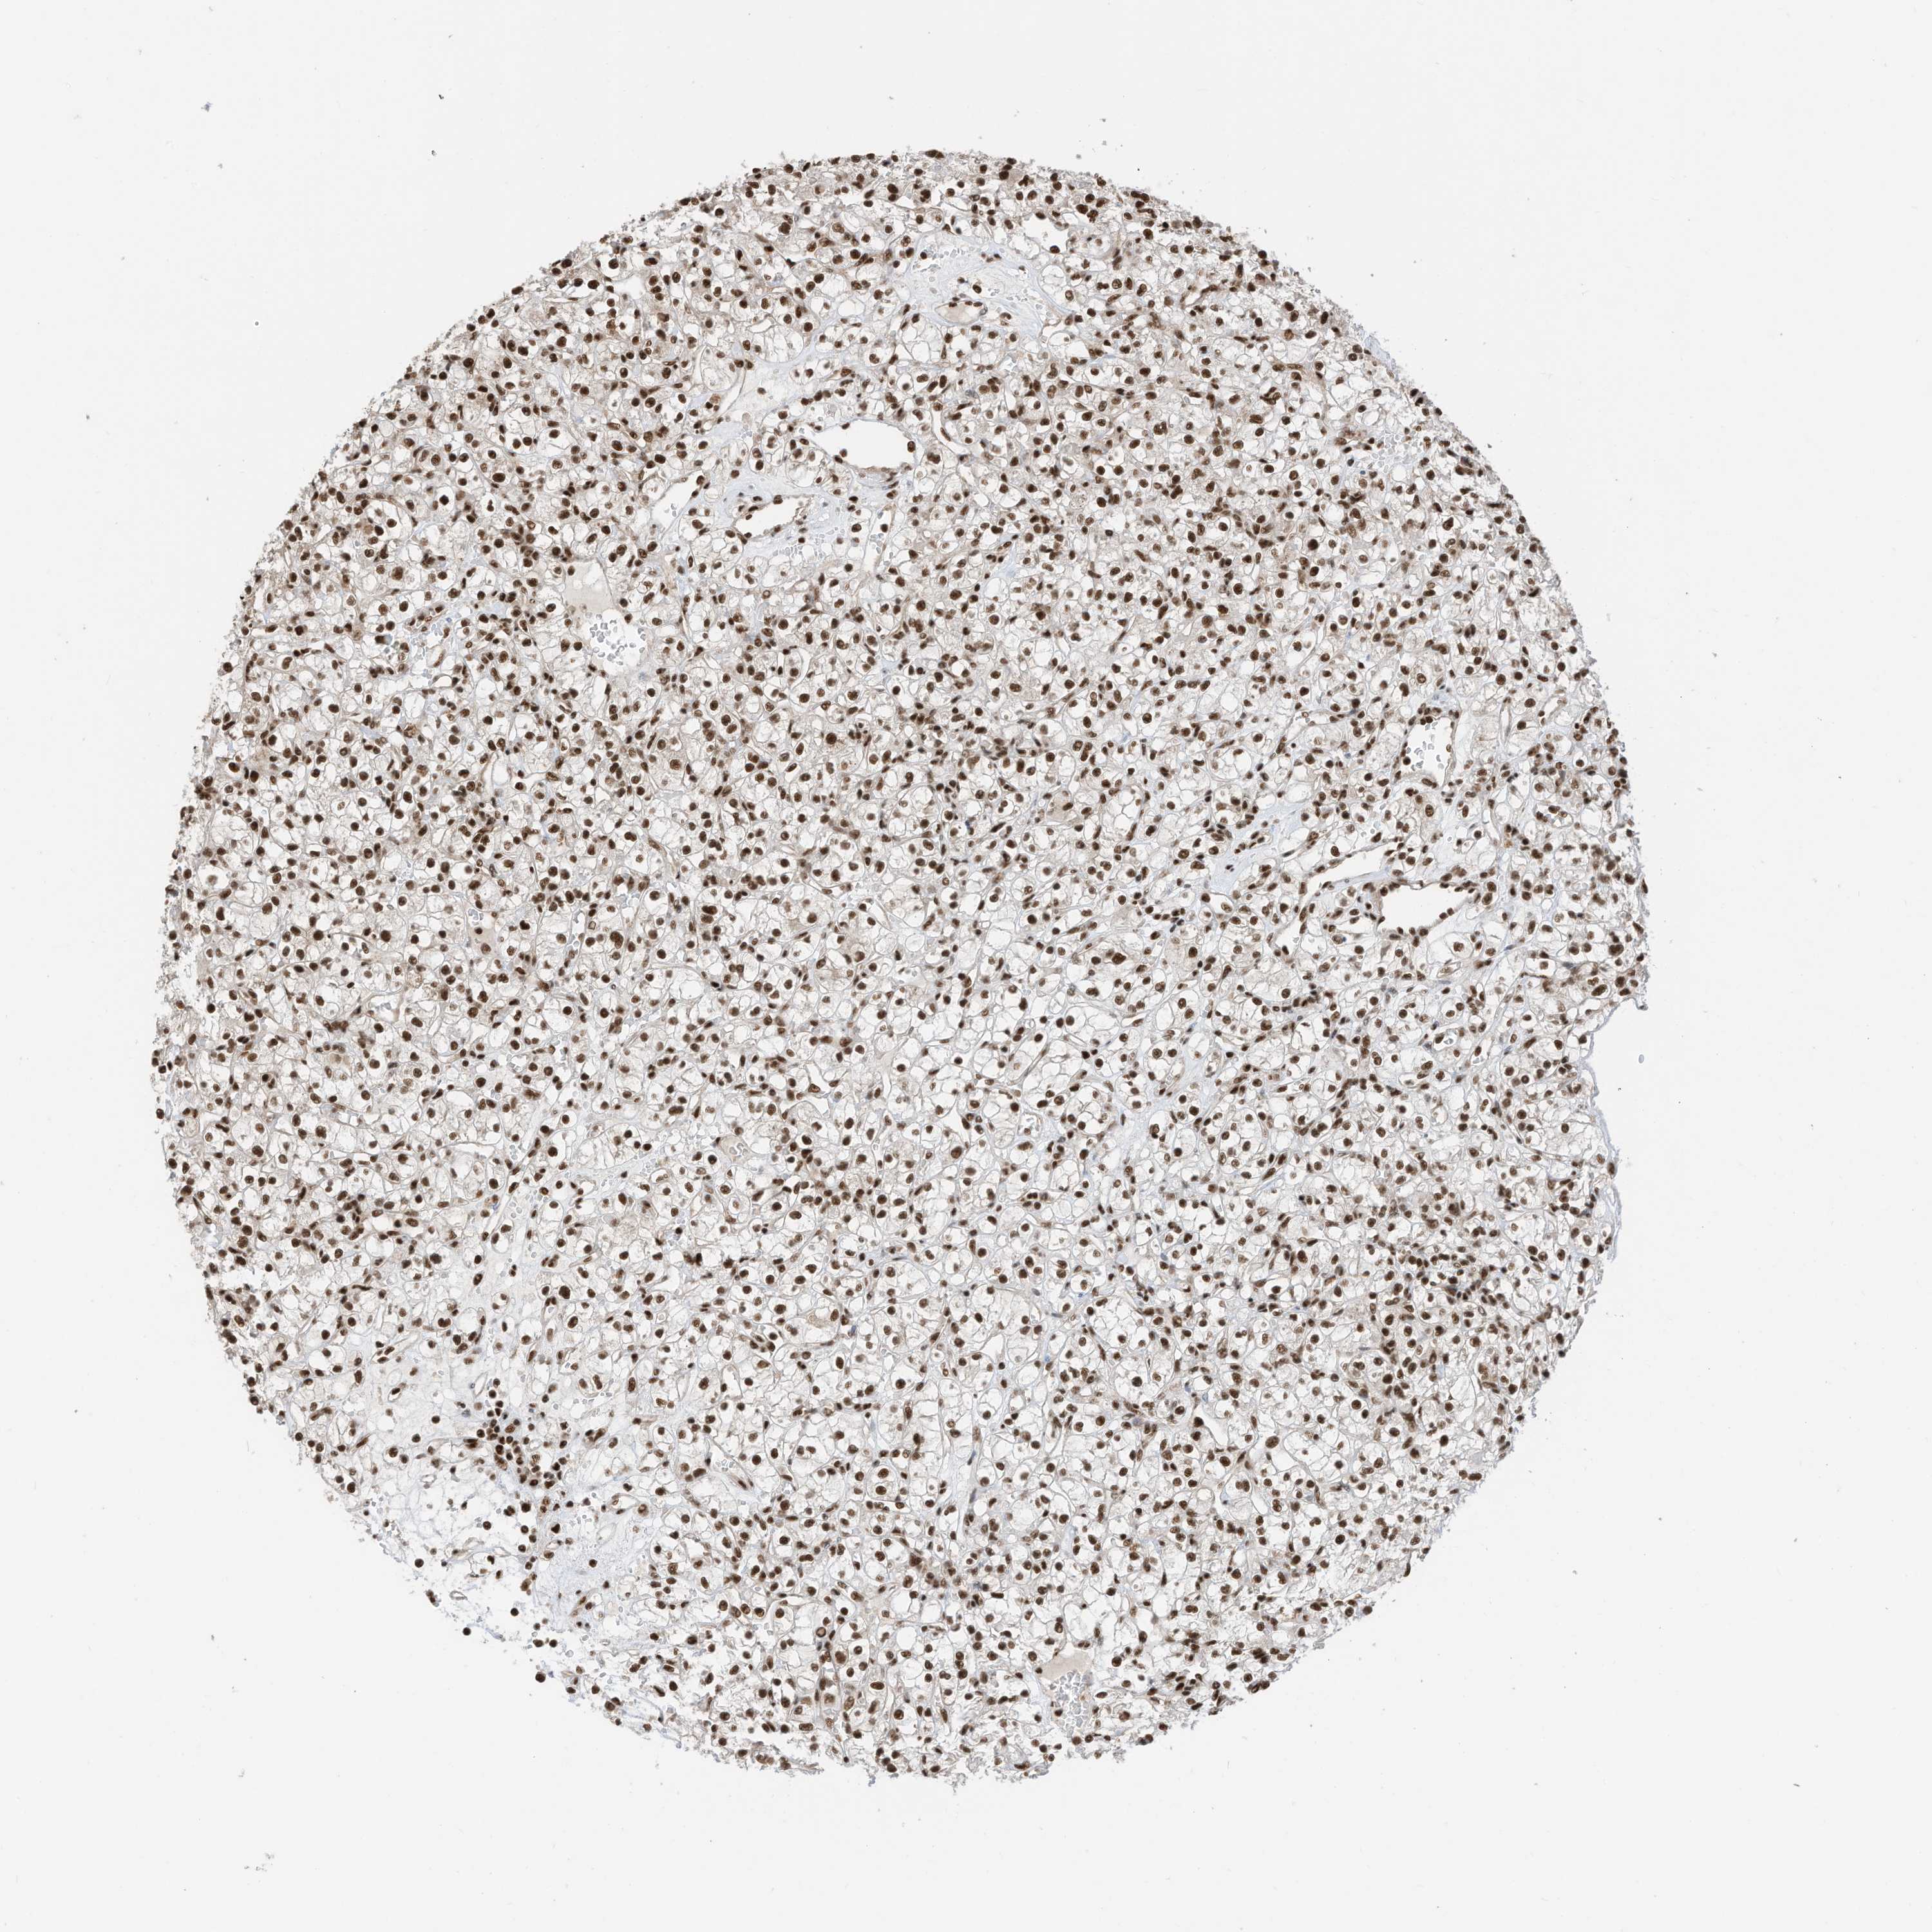

KIDNEY RENAL CLEAR CELL CARCINOMA (TCGA) - Interactive survival scatter ploti

The Survival Scatter plot shows the clinical status (i.e. dead or alive) for all individuals in the patient cohort, based on the same data that underlies the corresponding Kaplan-Meier plots. Patients that are alive at last time for follow-up are shown in blue and patients who have died during the study are shown in red.

The x-axis shows the expression levels (FPKM) of the investigated gene in the tumor tissue at the time of diagnosis. The y-axis shows the follow-up time after diagnosis (years). Both axes are complimented with kernel density curves demonstrating the data density over the axes. The top density plot shows the expression levels (FPKM) distribution among dead (red) and alive patients (blue). The right density plot shows the data density of the survived years of dead patients with high and low expression levels respectively, stratified using the cutoff indicated by the vertical dashed line through the Survival Scatter plot. This cutoff is automatically defined based on the FPKM cutoff that minimizes the p-score. The cutoff can be changed by dragging the vertical line or by entering a cutoff value in the square labeled "Current cut-off".

Under the Survival Scatter plot the p-score landscape (black curve; left axis) is shown together with dead median separation (red curve; right axis). Dead median separation is the difference in median mRNA expression between patients who have died with high and low expression, respectively. It is calculated as follows: median FPKM expression of dead patients with high expression - median FPKM expression of dead patients with low expression. This is intended to aid the user in visually exploring custom cutoffs and the associated p-scores and dead median separation.

Individual patient data is displayed and can be filtered by clicking on one or more of the category buttons on the top of the page. Categories describing expression level and patient information include: high, low, alive, dead, female, male and tumor stages. The scale of the x-axis can be toggled between linear and log-scale by clicking on the "x log" button. Mouse-over function shows TCGA ID, patient information and mRNA expression (FPKM) for each patient.

& Survival analysisi

Kaplan-Meier plots summarize results from analysis of correlation between mRNA expression level and patient survival. Patients were divided based on level of expression into one of the two groups "low" (under cut off) or "high" (over cut off). X-axis shows time for survival (years) and y-axis shows the probability of survival, where 1.0 corresponds to 100 percent.

SF3A3 is potential prognostic, high expression is favorable in Kidney Renal Clear Cell Carcinoma (TCGA)

: 26.64

TCGA RNA samplesi

RNA-seq data is reported as average FPKM (number Fragments Per Kilobase of exon per Million reads), generated by the The Cancer Genome Atlas (TCGA) .

Normal distribution across the dataset is visualized with box plots, shown as median and 25th and 75th percentiles. Points are displayed as outliers if they are above or below 1.5 times the interquartile range. FPKM values of the individual samples are presented next to the box plot.

Average pTPM 35.7

Number of samples 521